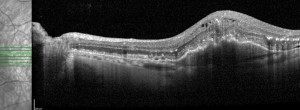

MANTRA: evaluación de la asociación entre la sensibilidad y el flujo retiniano en la DMAE